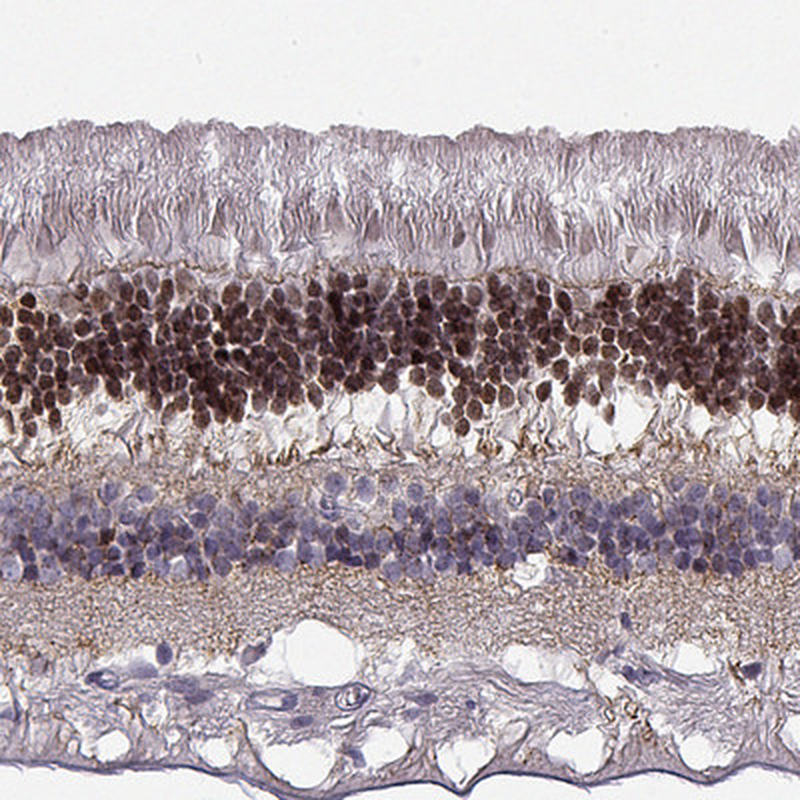

Immunohistochemical staining of human retina shows strong nuclear positivity in photoreceptor cells.